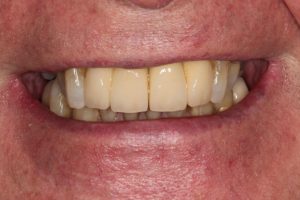

Upper Front Tooth Implant

Both upper front teeth were in a bad way, the upper left one had to be removed as was beyond repair, this was replaced with an implant and a temporary crown on the same day; the upper right front tooth was repaired with a crown. Photos show the result with the definitive crowns after 3 months of treatment.